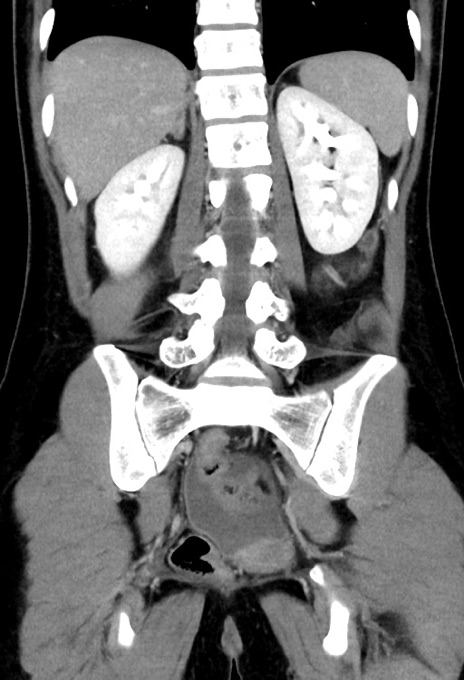

症例17(冠状断像)

【症例】20歳代女性

【主訴】嘔吐、下腹部痛

【現病歴】昨日夕食後に嘔吐し下腹部痛が出現。本日になっても嘔吐持続し改善しないため来院。

【身体所見】意識清明、BT 37.2℃、BP 108/67mmHg、腹部:平坦、やや硬、下腹部正中から右にかけて圧痛あり、反跳痛軽度あり、tapping pain(+)。

【データ】WBC 13600、CRP 14.94

横断像